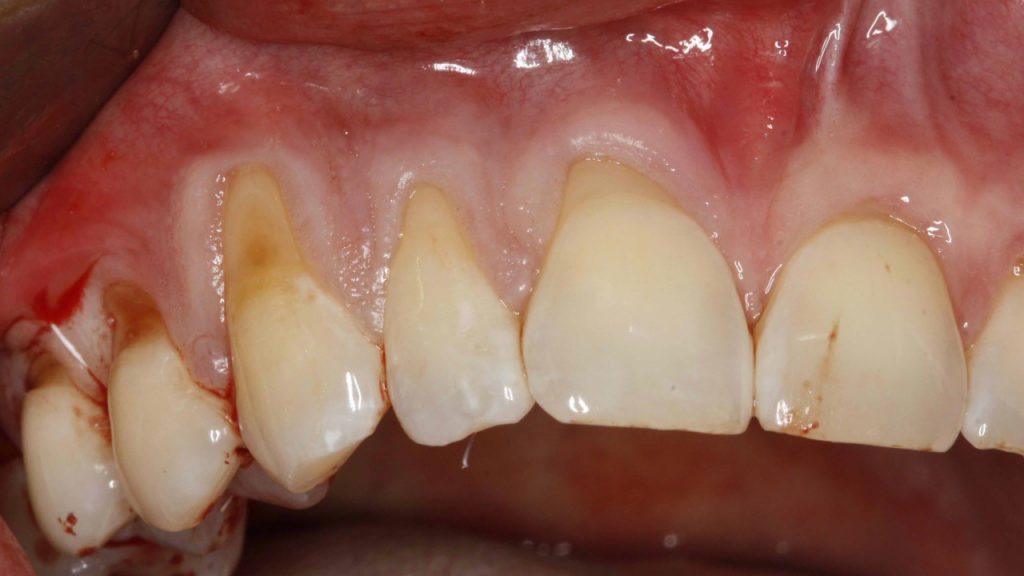

– Bardzo istotne jest regularne, co najmniej raz w roku, usuwanie kamienia nazębnego – wykonanie tzw. skalingu w gabinecie, który jest profesjonalnym zabiegiem zapobiegającym chorobom przyzębia, które w jamie ustnej objawiają się obrzękami i krwawieniem dziąseł, ale też ruchomością zębów – mówi lek. dent. Kamila Kruk z gabinetu Stomatologia Królewska 24. – W wyniku tych chorób przyzębia pacjenci tracą swoje zęby, a choroby wymienione wyżej mogą nasilać te procesy.